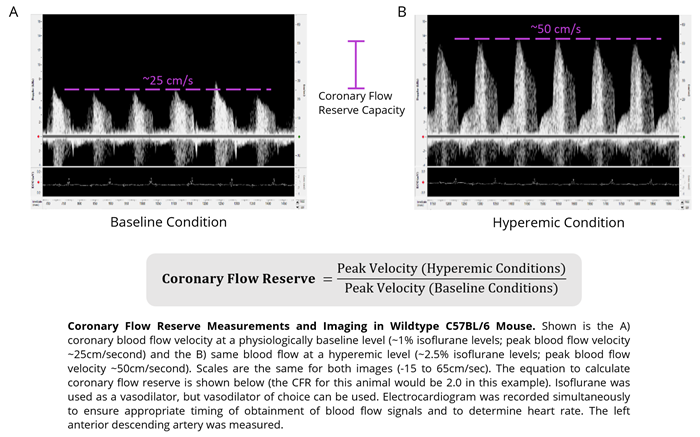

Coronary flow reserve

Area

- Pressure Overload-Hypertrophy

- Atherosclerosis

- Myocardial Ischemia

Flow parameter

The ratio of hyperemic to baseline coronary flow velocity

Imaging gallery - Doppler Flow Velocity System

Mouse - Coronary Flow Reserve Imaging. Image Credit: Scintica Instrumentation Inc.